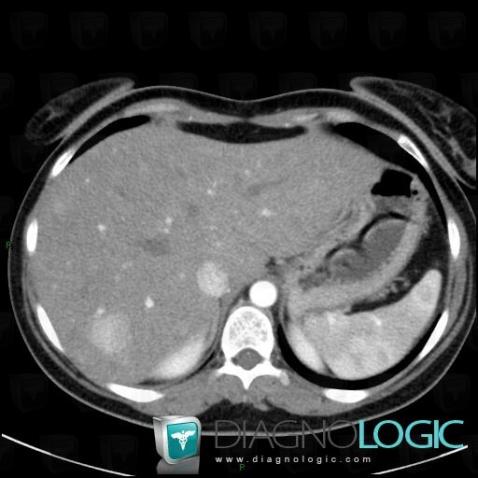

Adénome hépatique, Foie, Scanner

Voici les informations spécifiques à l'image clé ci dessus:

- Diagnostic Adénome hépatique, Localisation(s) Foie, comportant les gammes Lésion avec prise de contraste artérielle